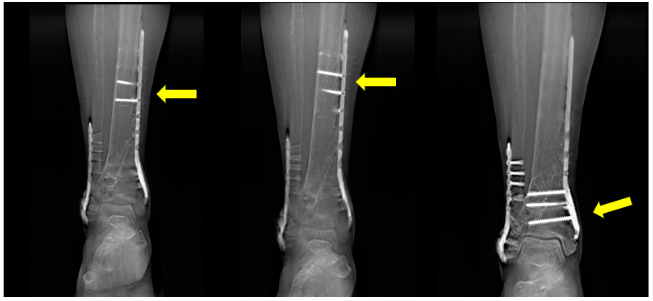

2、有助于对金属植入物骨折的显示

3、有助于对于金属植入物新生骨生长情况观察